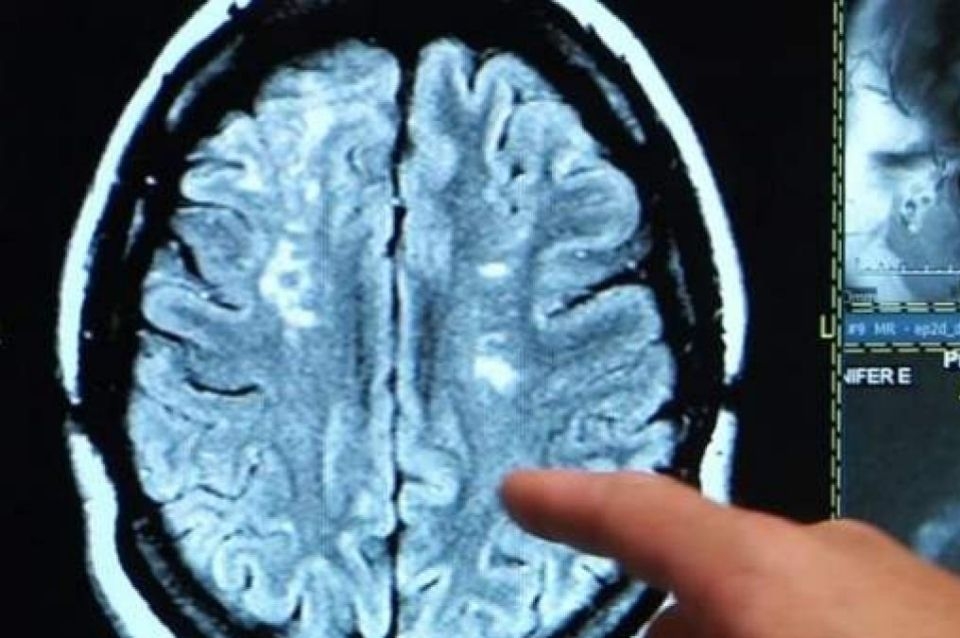

En la investigación participaron 785 personas (infectados y no infectados) y todos ellos se sometieron a dos escáneres cerebrales con 38 meses de diferencia. De los 401 participantes que habían dado positivo entre las dos exploraciones, se encontraron efectos en el cerebro (en promedio, 4,5 meses después de la infección).

Entre los deterioros se encontraron una mayor reducción en el grosor de la materia gris y un daño tisular en regiones del cerebro asociadas con el olfato. En comparación con los participantes no infectados, los efectos cambiaban entre un 0,2% y un 2%.

También se encontró evidencia de pequeñas hemorragias, daño neuronal y muerte, incluso en personas que no tenían una enfermedad grave.